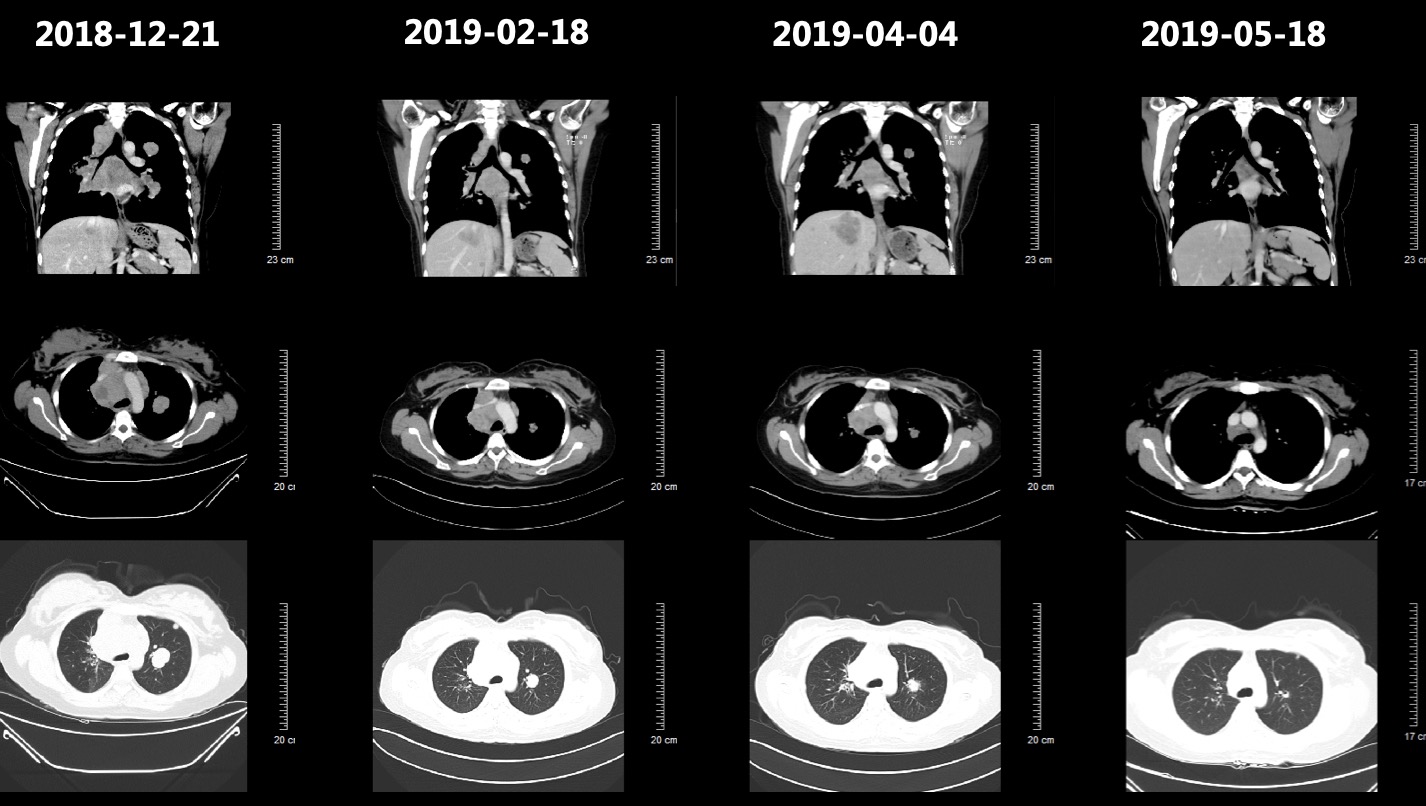

• 2018-12-17患者顺产1足月女婴,次日就诊于当地医院,查胸片发现右肺占位性病变。肿瘤标志物检测提示:CA15-3、CA125、Cyfra21-1、TPS升高(表1)。CT检查提示1.右肺上叶近肺门处团块状软组织密度影,考虑中央型肺癌可能,伴阻塞性肺炎,并纵隔内、双侧肺门多发淋巴结转移,双肺、肝脏多发转移瘤;L1椎体及左侧附件密度增高,考虑为转移瘤;2.脾大(图1);头颅MRI检查提示头颅MRI未见占位性病变。气管纤维支气管镜检查提示右主支气管新生物生长,表明凹凸不平,触之易出血,予活检及肺泡灌洗;隆突粘膜改变,肿瘤浸润可能。送检(右主支气管)组织内见部分瘤细胞呈巢团状排列,异型明显,胞浆丰富、红染,核异型性明显核仁可见,间质纤维组织增生伴大量淋巴细胞浸润(图2)。免疫组化:CK(+)、CK7(-)、TTF(-)、P40(+)、CK5/6(部分+)、Ki-67(+, 80%) 。原位杂交:EBER(+)。免疫组化 (补,22C3):PD-L1 (+, 95%)病理诊断考虑淋巴上皮瘤样癌。

图2 纤维支气管镜组织活检病理图像,病理诊断考虑淋巴上皮瘤样癌